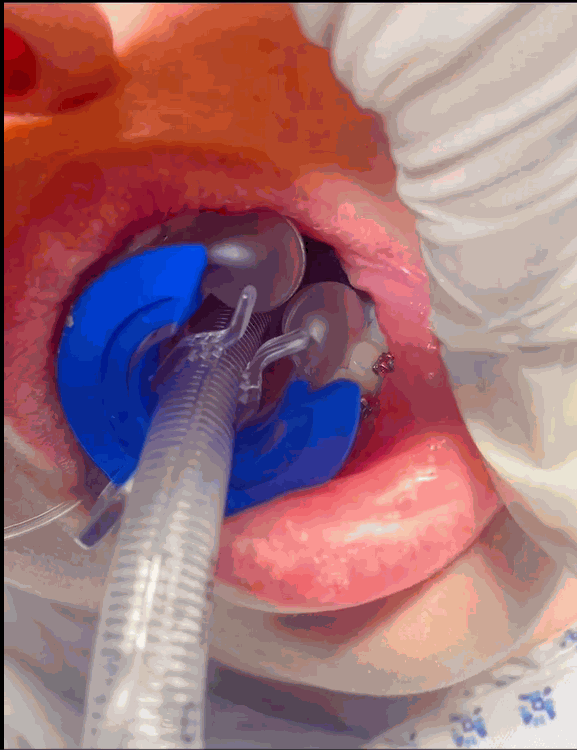

El dispositivo CLIP-FAB es un dispositivo desechable de fácil uso, que se adapta al tubo endotraqueal (ET) mediante un clip y un balón intraoral, fijándolo y evitando que se mueva o se desplace accidentalmente mientras el paciente permanezca conectado.

El dispositivo CLIP-FAB está compuesto por 4 piezas.

GLOBO para colocar detrás de los dientes

SOPORTE para colocar entre dientes y labios.

PINZA de fijación del TE.

Sistema de hinchado.

El dispositivo CLIP-FAB se coloca fácilmente después de la introducción del tubo endotraqueal. Una vez que el tubo endotraqueal se ha colocado en su posición definitiva, se fija lateralmente al dispositivo mediante el clip interior.

Con el inflado del globo interno, el dispositivo CLIP-FAB garantiza la fijación total de todo el sistema

(TE + CLIP-FAB) sin la necesidad de ningún otro material externo y evitando los desplazamientos.